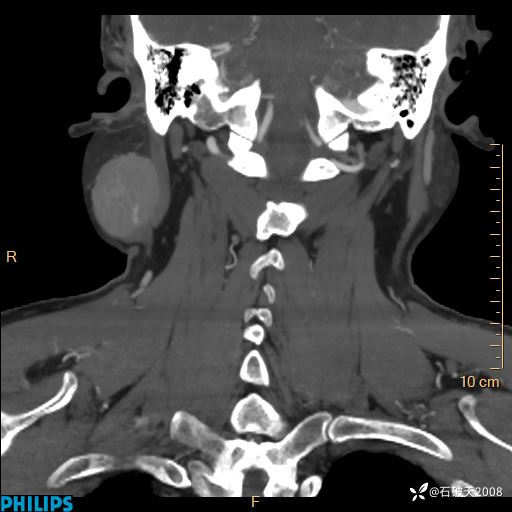

静脉期